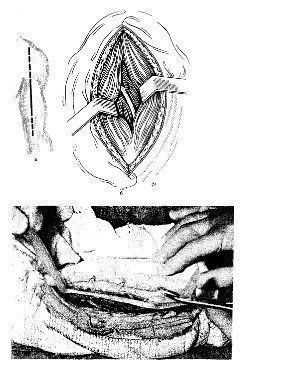

Положение больного — на спине, рука отведена в сторону и лежит на приставном столике в положении пронации. Величина разреза зависит от объема операции и уровня повреждения. Разрез начинают по переднему краю дельтовидной мышцы, а затем проводят по наружному краю двуглавой мышцы плеча. По ходу кожного разреза рассекают фасцию плеча. Латеральную подкожную вену руки отводят кнутри или перевязывают и пересекают. Такой разрез позволяет обнажить в проксимальном отделе раны передневнутреннюю часть дельтовидной мышцы, а в дистальной части — наружный край двуглавой и плечевой мышц. Разделив дельтовидную и двуглавую мышцы, обнажают плечевую кость (рис. 1) до уровня ее нижней трети.

1. Передненаружный доступ к диафизу плечевой кости (по проекции лучевого нерва).

а — линия разреза; б — обнажение плечевой кости после выделения лучевого нерва.